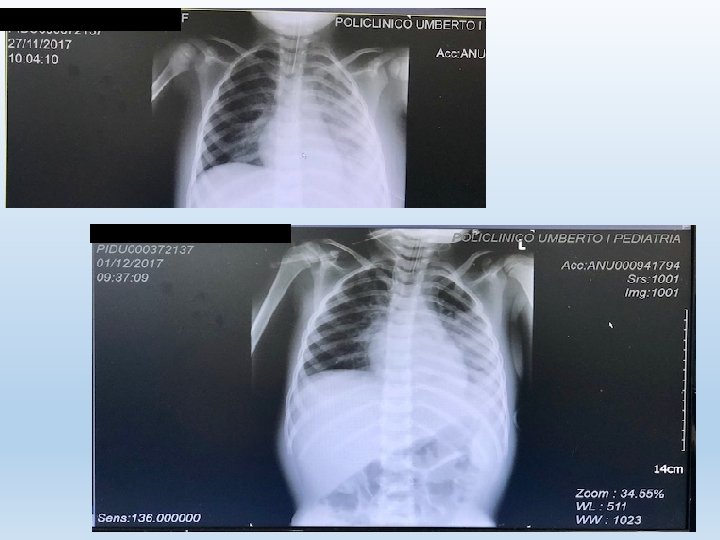

Rx Torace (eseguito in PS) abbondante versamento pleurico a sinistra con spostamento controlaterale del mediastino, opacamento della base polmonare sinistra

13. 11. 17 EGA (p. H 7. 25, p. CO 2 52, PO 272, HCO 3 22. 8, EB - 4. 5) Sa. O 2 97% con Fi. O 2 0. 80 RX Torace: aspetto opaco emitorace sinistro, spostamento mediastino e trachea verso destra. Posizionamento drenaggio pleurico (aspirati 20 -30 ml di liquido) PCR 15. 47 mg%, PCT 17. 44

15. 11. 17 Rx torace: persiste completo opacamento del polmone sinistro. Parametri invariati, Fi. O 2 0, 5 EGA (p. H 7. 37, p. CO 2 48, PO 294, HCO 3 26. 6, EB 2. 1; P/F Ratio 188)

16. 11. 17 Rx torace: addensamento parenchimale di verosimile origine disventilatoria in sede apicale destra, ulteriore lieve riduzione della espansione polmonare del parenchima a sinistra. Parametri invariati, Fi. O 2 0, 5 EGA (p. H 7. 45, p. CO 2 54, PO 2102, HCO 3 31. 7, EB 8. 6; P/F Ratio 104) PCR 20. 69 mg%, PCT 2. 35

17. 11. 17 Rx torace: permane addensamento di gran parte del polmone sinistro, ili congesti, non versamento; ingrandimento di fegato e milza. Parametri ventilatori invariati, Fi. O 2 0. 7 EGA (p. H 7. 30, p. CO 2 76, PO 268, HCO 3 31. 4, EB 8. 5, P/F Ratio 113) Inizia i. NO 20 ppm BAL e Coltura Liquido Pleurico POSITIVI per Pneumococco PCR 18. 9 mg%, PCT 1. 3

20. 11. 17 Rx torace: riespansione del polmone di sinistra, addensamenti basali meno estesi; alcune aree di ipertrasparenza tondeggianti, verosimilmente riferibili a pneumatoceli. Parametri ventilatori invariati, Fi. O 2 0. 65 EGA (p. H 7. 45, p. CO 2 52, PO 2 73, HCO 3 36. 1, EB 12. 1, P/F Ratio 113) i. NO 20 ppm (Met. Hb nella norma) PCR 5. 29 mg%, PCT 0. 48

24. 11. 17 Rx torace: netta riduzione degli addensamenti in medio basale sinistra, e del versamento omolaterale, permane ipoespansione del lobo inferiore sinistro. Parametri ventilatori: PIP +21, PEEP 7, Ti 0. 72, MAP 12, FR 28 atti/m, Fi. O 2 0. 55 EGA (p. H 7. 38, p. CO 2 58, PO 2 148, HCO 3 31, EB 7. 8, P/F Ratio 229) i. NO 13 ppm (Met. Hb nella norma) PCR 2. 58 mg%, PCT 0. 21